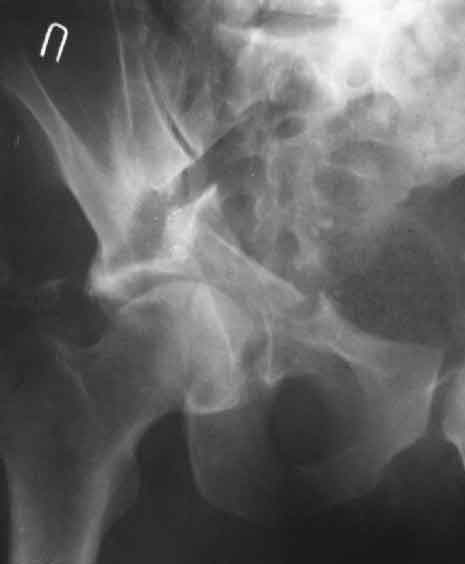

Дополнение, минимальный набор необходимых прекций, необходимых для лечения повреждений вертлужной впадины

Подвздошная Запирательная